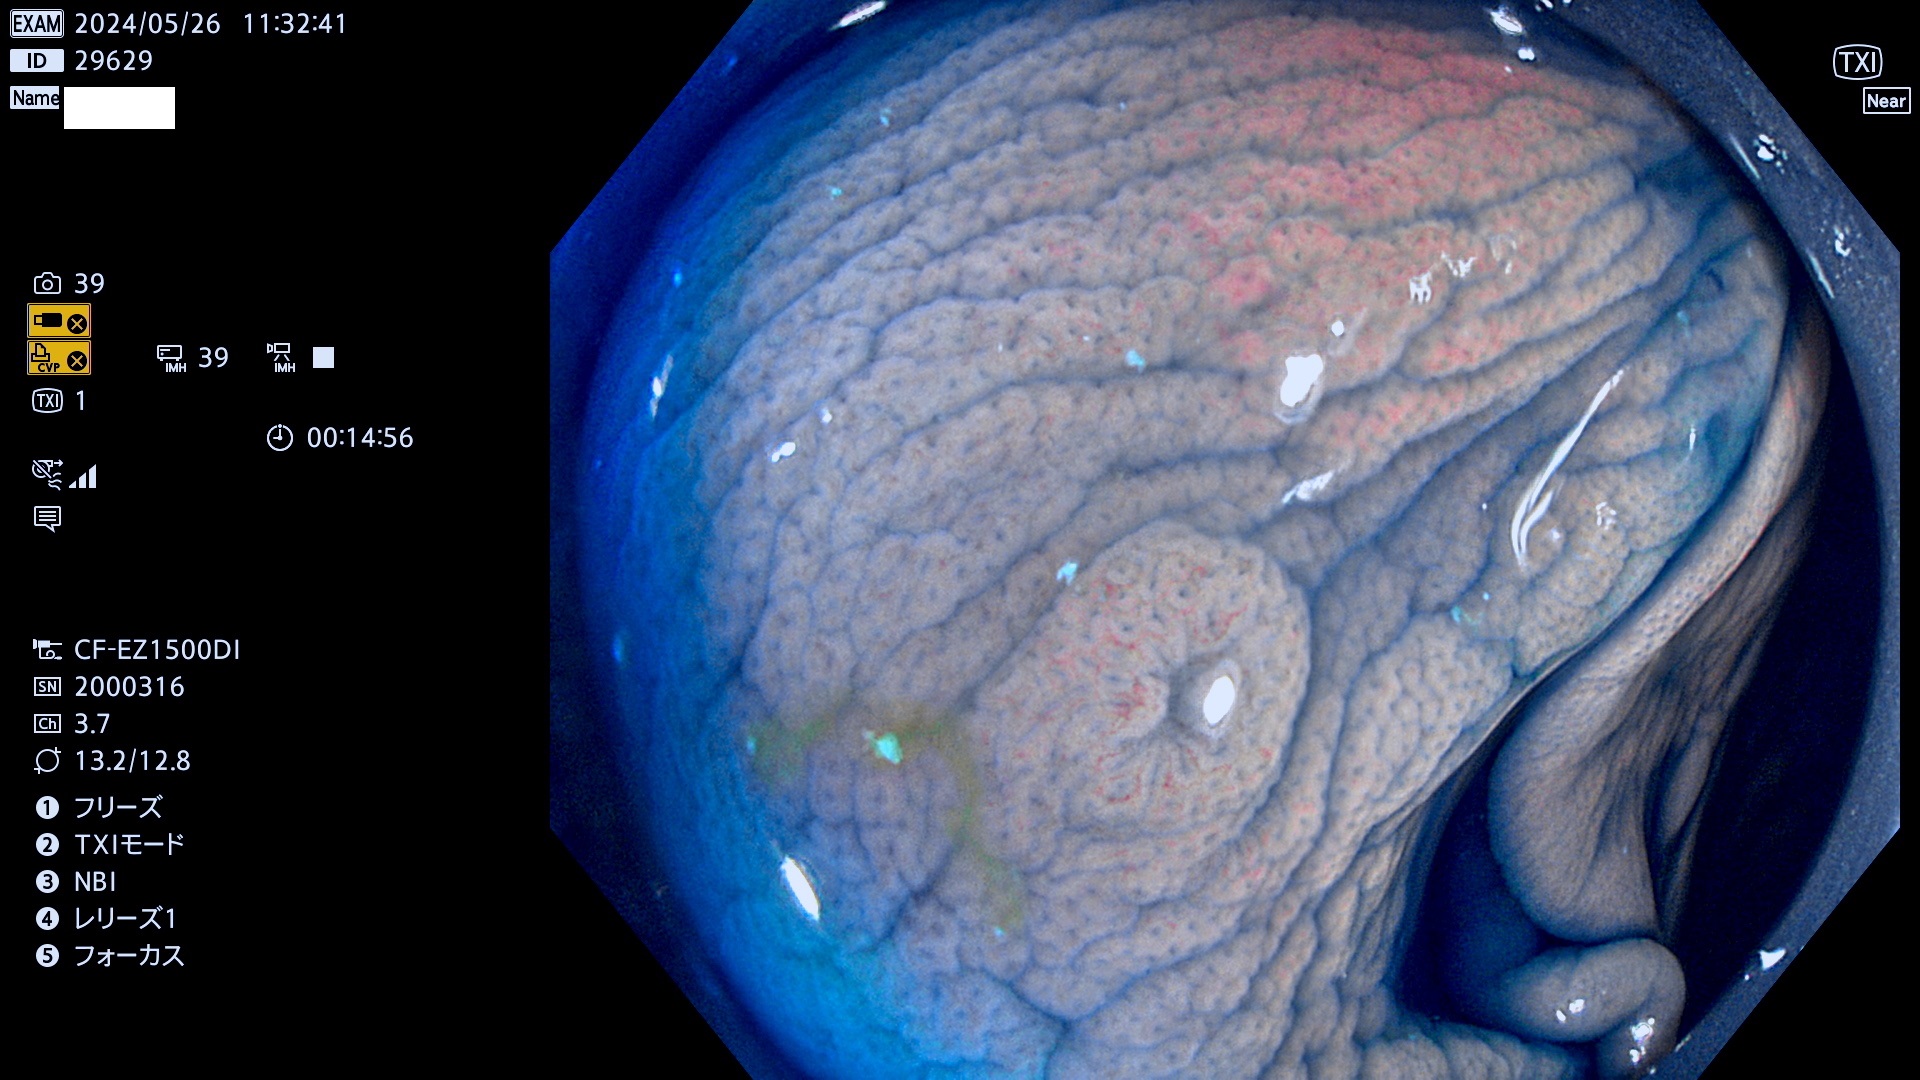

表面型腺腫(Flat Adenoma)の中で、完全に平坦な物をUb、陥凹している物をUcと呼びます。平坦隆起型(Ua)よりも、発見が難しく危険な病変です。

ビランと鑑別の難しい陥凹型腺腫